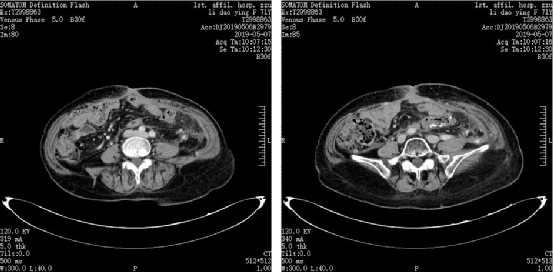

图片

图2.2018年11月22日复查CT

当时我中心正在进行恩沃利单抗II期临床试验,该患者的基因检测结果显示为MSI-H,于2019年2月通过筛选后该患者入组“恩沃利单抗治疗dMMR/MSI-H 晚期结直肠癌及其他晚期实体瘤患者的临床疗效和安全性的多中心II期临床研究”。2019年3月起,为患者进行恩沃利单抗150mg,皮下注射,QW治疗,2019年5月7日复查CT显示,病灶显著缩小,疗效评估为部分缓解(PR)。该患者半年后复查CT提示腹壁及腹腔结节几乎完全消失,疗效评估为CRu。